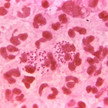

Übertragung durch Rötelmäuse Hantavirus: Infektionen steigen stark an

Aktuell steigen die Infektionen mit dem Hantavirus stark an. Besonders betroffen sind Regionen in Süddeutschland. Das Virus wird durch Nagetiere, insbesondere... Mehr»